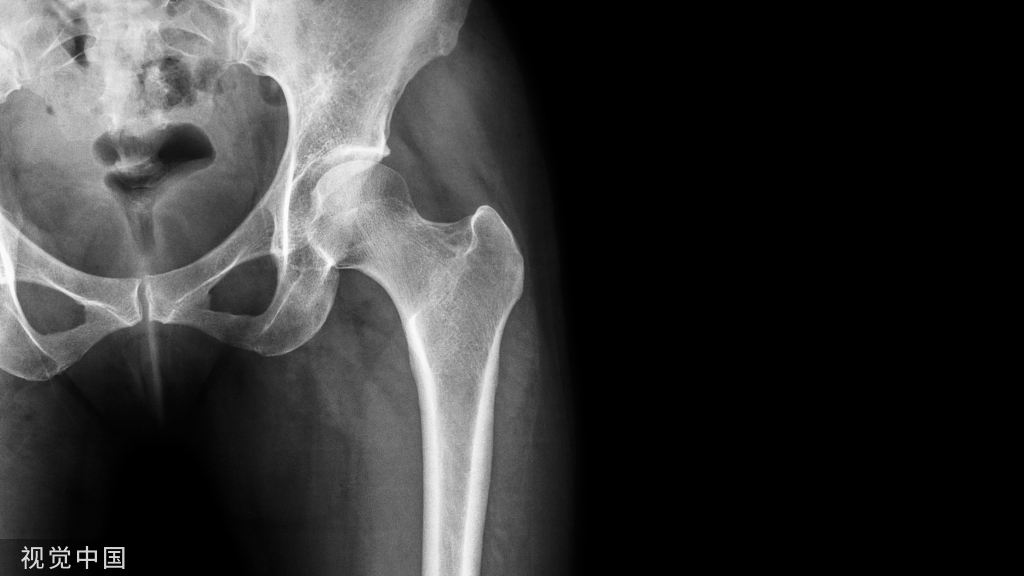

AO、Garden 和 Pauwels 骨折分类系统是最常用的。移位的股骨颈骨折在 ORIF 或闭合复位内固定后通常比未移位的骨折具有更差的结果。显着的初始位移、Pauwels 3 型骨折和颈后内侧粉碎与不良结果相关。注意后内侧粉碎和高pauwles角,该类患者增加骨不连、畸形愈合、缺血性坏死和早期失败的风险